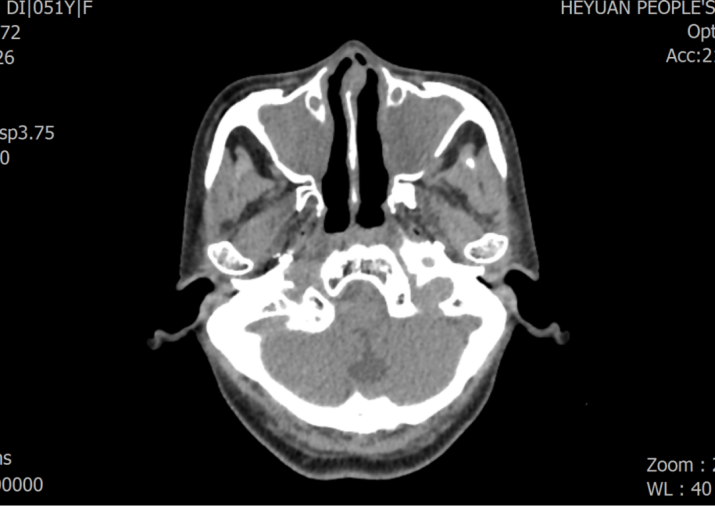

患者周某某,女,51岁,因“反复咳嗽、咳痰30余年,加重5天”入住我院呼吸与危重症医学科,胸部CT示双肺支气管扩张、右位心;入院诊断:支气管扩张症并感染。罗少华主任医师查房分析患者病情指出,患者双肺支气管扩张,右位心伴全内脏转位,需考虑罕见病——“卡塔格内综合征”,结合后续的完善鼻窦CT:双侧筛窦、上颌窦、蝶窦、右侧额窦炎,符合“卡塔格内综合征”的诊断标准。经规范治疗,患者病情好转,予做好健康宣教后出院。

鼻窦CT见双侧筛窦、上颌窦、蝶窦、右侧额窦炎,双侧乳突炎